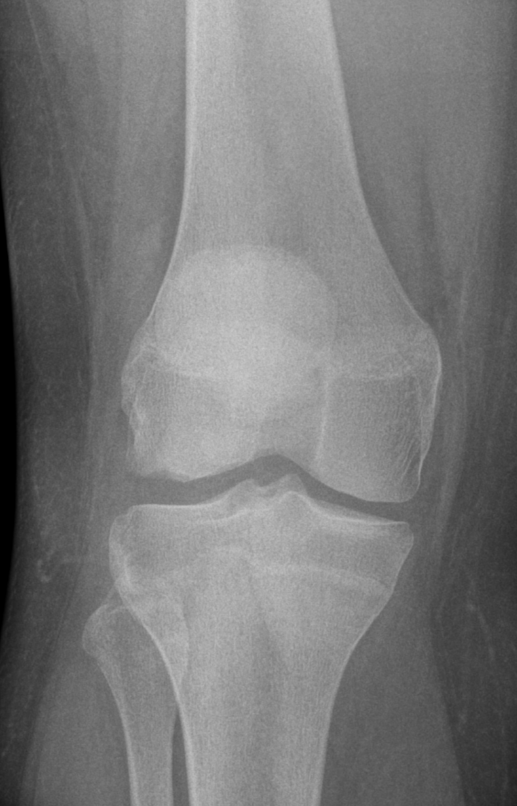

3. Osteochdonral Injury lateral femoral condyle